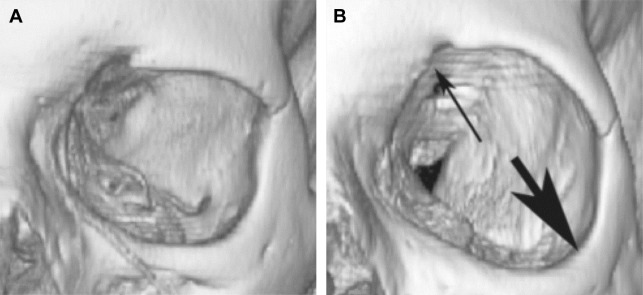

Facial aging is a dynamic process that involves skin, subcutaneous soft tissues, and bony structures. The bony remodeling of the orbit results in orbital elongation, loss of projection, and change of the bone–soft tissue relationship ( Fig. 1 ), which likely contributes to the fat prolapse, hollow sulci, ptosis, brow descent, and lateral upper eyelid hooding that is commonly seen in aging. The skin and subcutaneous tissues around the periocular area become increasingly hollow, allowing the underlying bone, muscle, remaining fat, and blood vessels to become more apparent. The gradual descent and atrophy of subcutaneous tissue alters the smooth ogee curve of the youthful face.